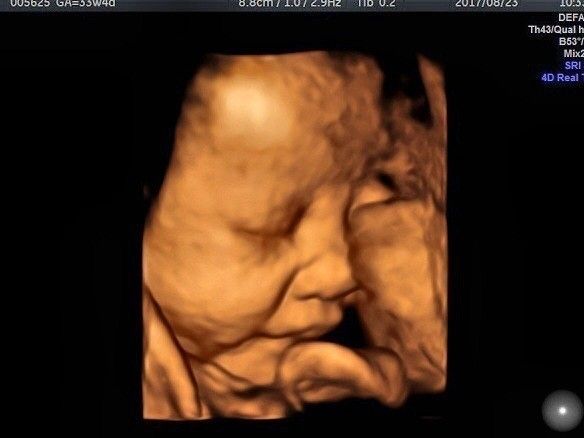

立体的な画像の3D超音波

「3D超音波は、2次元(①縦軸②横軸)にプラスもう1次元(③奥行軸)の情報を組み立てることで、立体的な画像を見ることができるもの。断面的な2Dと異なり、表面的な状態が見えるので、赤ちゃんの顔立ちなどがわかります。この画像は、上の2D超音波と同じときに撮影した、妊娠33週の赤ちゃんの写真です。こうして見ると、違いは一目瞭然ですね」